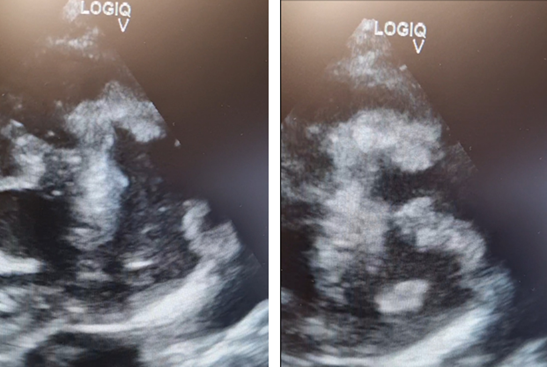

Figure 2 X ray-bronchovascular drawing emphasized right hiloperihilar and paracardiobasal with a field of plate-like small atelectasis.